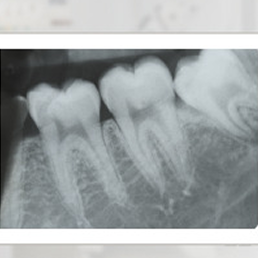

Badanie RTG obejmujące obszar 1- 3 zębów. Obrazuje korony, wierzchołki korzeni oraz tkanki wokół obrazowanych zębów.

- RTG punktowe zęba – pozwala na dokładne zobrazowanie jednego zęba lub jego fragmentu. Wykorzystywane najczęściej przy leczeniu kanałowym lub podejrzeniu próchnicy w trudno dostępnych miejscach.